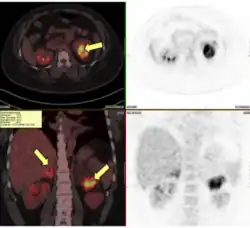

CT scan shows enlarged adrenals with masses consistent with congenital adrenal hyperplasia due to 21-hydroxylase deficiency (image credit: NICHD/A. Mallappa, D. Merke)